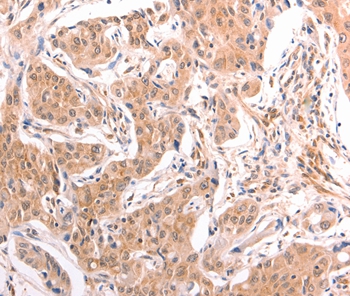

分类: 科研抗体货号: P42790别名: SUFUH; SUFUXL; PRO1280应用: WB,IHC反应种属: Human